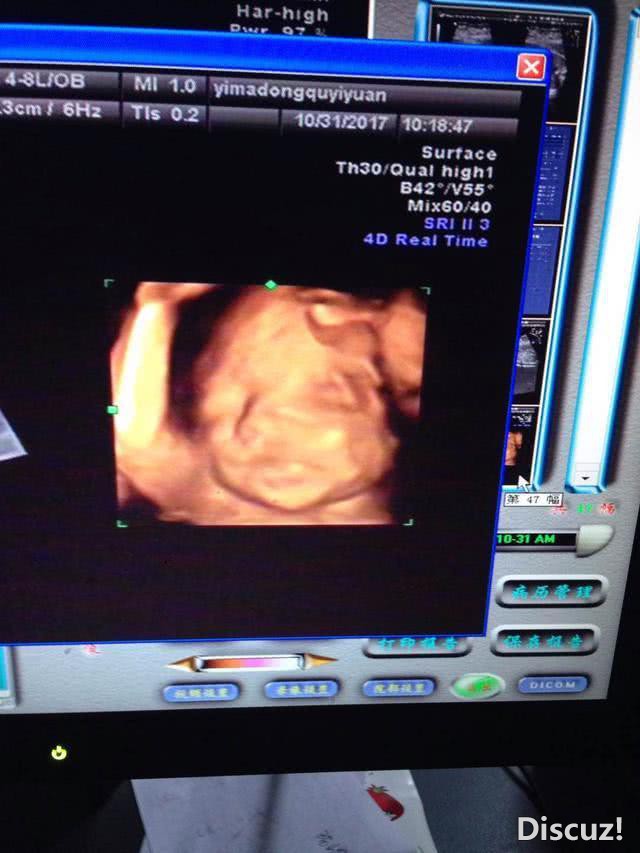

这么多不一样,要是我做彩超绝对不会去询问孩子的性别,不论是男是女,只要健健康康的就好,希望大家都是自己心里所想的。